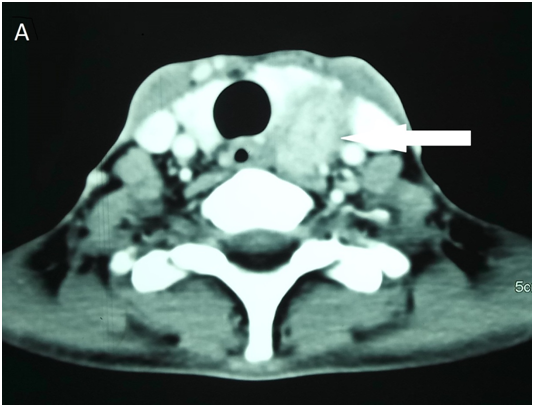

A 30-year-old female presented to the emergency department with severe epigastric pain and persistent vomiting for two days. Physical examination revealed tenderness and guarding in the epigastric area. Bowel sounds were sluggish. Laboratory investigations revealed raised serum amylase (910U/l, reference range 28–100U/l) and serum lipase (286U/l, reference range <67U/l) levels. Computed tomography of the abdomen revealed bulky pancreas with peripancreatic fat stranding, thus confirming acute pancreatitis. Further biochemical investigations revealed high serum calcium (3.5mmol/L) with low serum phosphate (0.56mmol/L). Serum parathyroid hormone levels were markedly elevated (638ng/L) with normal 25 (OH) vitamin D levels (84nmol/L). Computed tomography of the neck revealed 5x3 cm heterogeneously enhancing soft tissue lesion in the left retrotracheal space displacing the left lobe of thyroid gland anteriorly (Figure 1A). Technetium (Tc-99m) labeled sestamibi scan revealed the presence of hot focus in the left inferior pole of thyroid in the delayed image, consistent with parathyroid adenoma (Figure 1B). The patient received fluid replacement with saline and bisphosphonates. After therapy, the serum calcium levels decreased, and the acute pancreatitis subsided. Patient underwent surgical excision of adenoma, and histopathology confirmed the diagnosis.

Figure 1 Computed tomography of the neck revealed 3x2cm heterogeneously enhancing soft tissue lesion within the left retrotracheal space merging with lower pole of left lobe of thyroid.